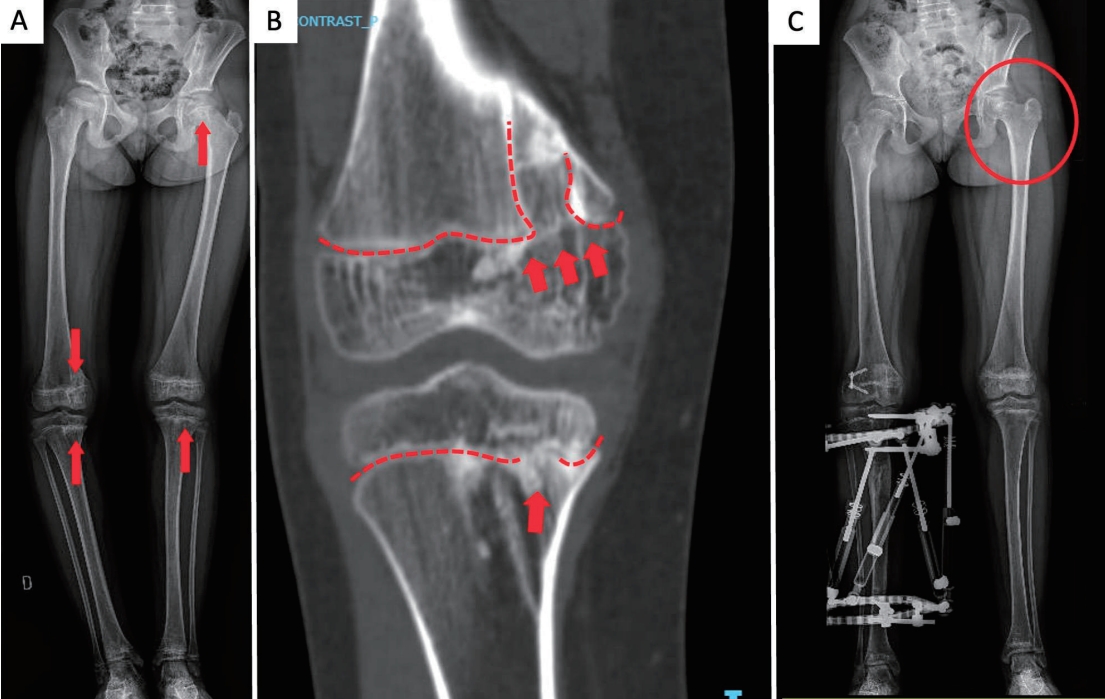

As the patient grew, scoliosis became evident, and she developed right-sided genu varum. Radiographs demonstrated asymmetric physeal bone bridges across the medial distal femoral and proximal tibial physes on the right, with additional bridges across the left tibial physis and the left femoral head physis; the latter was associated with coxa breva (Figs. 2A and B). These bridges produced focal growth arrest rather than diffuse physeal involvement.

Orthopedic correction comprised lateral distal femoral hemiepiphysiodesis to restrain lateral growth and tibial distraction osteogenesis with an external fixator to restore medial length and alignment, achieving correction of genu varum and limb-length equality (Fig. 2C).

Fig. 2.

Radiographic features and management. (A) Lower-limb radiograph showing osseous bridges across the right medial distal femoral and proximal tibial physes (genu varum), left tibial physis, and left femoral head physis (coxa breva) (arrows). (B) Detail of medial femoral/tibial bridges; the dashed lines indicate physes interrupted by bridges (arrows). (C) Postoperative radiograph showing lateral distal femoral hemiepiphysiodesis and tibial external fixator for medial distraction osteogenesis; the circle marks the left coxa breva.